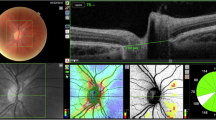

Optic nerve head drusen (ONHD) are considered the most common cause for pseudopapilloedema in children. We aimed to investigate and further characterize a new type of optic nerve head lesion on enhanced depth imaging optical coherence tomography (EDI-OCT) named peripapillary hyperreflective ovoid mass-like structures (PHOMS), and ONHD in asymptomatic children with pseudopapilloedema.

On EDI-OCT, PHOMS were detected in 63 out of 64 eyes (98.4%). In 60 eyes (93.8%), small hyperreflective foci inside the PHOMS were present. In all cases, we identified a new ring sign visible on infrared images, corresponding clearly to the edge of the PHOMS as seen on EDI-OCT. On ultrasound, we describe a new feature of PHOMS appearing as small hyperechogenic structures without posterior shadowing. In 13 eyes (20.3%), ONHD were present on EDI-OCT and ultrasound.